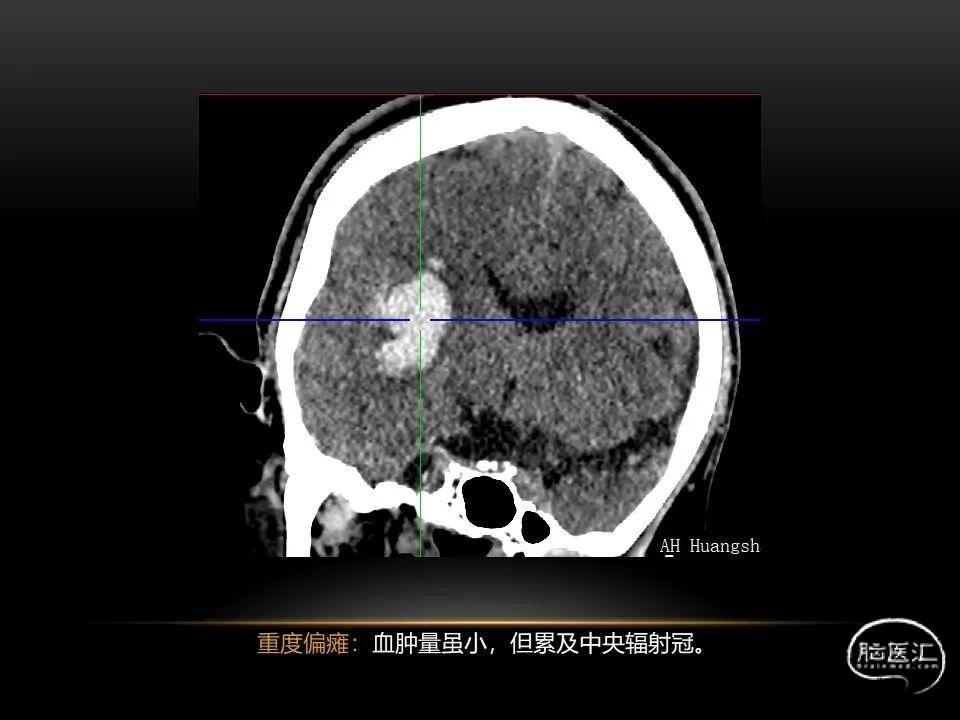

相近的脑出血量,

发生在不同部位有截然不同的症状,

同样也决定了预后也是截然不同的。

自发性脑出血不仅仅累及内囊后肢才会出现偏瘫及偏身感觉障碍,病变累及大脑脚或辐射冠同样有可能有类似症状和体征。内囊、辐射冠、大脑脚等结构之间是延续的,只是不同区域不同名称而已。定位诊断需要对解剖结构概念清晰,读片准确辨认,灵活掌握。